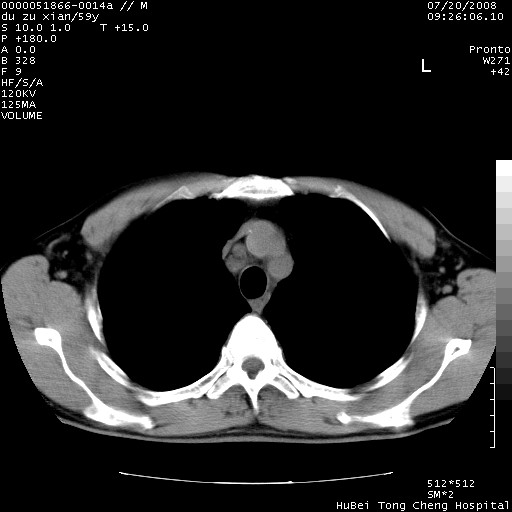

以下是引用宇宙ct在2008-8-25 23:21:00的发言:[br]右肺周围性肺癌并肋骨转移,纵隔淋巴结转移。

以下是引用zsl6918在2008-8-25 22:40:00的发言:[br]右肺周围性肺癌并肋骨转移,纵隔淋巴结转移。

以下是引用zy_zj在2008-8-26 15:24:00的发言:[br]单从病变本身,我倾向良性炎性病变,但肋骨转移了,所以说是考虑右肺周围性肺癌并肋骨、纵隔淋巴结转移可能性大。